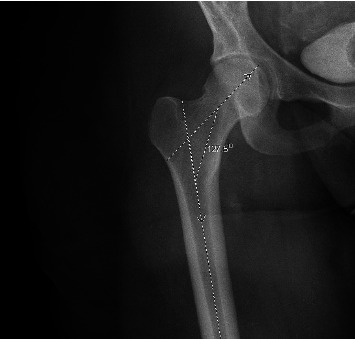

髓内钉固定是股骨骨折手术治疗的“金标准”。虽然钉子设计和患者解剖的许多方面都得到了特别的关注,但股骨近端几何形状的解剖变化和更大的转子高度变化的研究很少。了解大转子与患者人口统计学的潜在关系可能为改善种植体放置提供机会。回顾性审查x线和计算机断层图像的股骨近端进行。纳入标准包括18岁以上具有股骨近端影像学的骨骼成熟患者。纳入标准确定了296例患者。患者平均年龄34±20岁。大转子平均高度为40±8.1 mm。头-柱-骨干平均夹角为141±8.6度。在使用单变量分析确定显著因素后,多变量线性回归显示患者身高和头-柱-骨干角是大转子高度的统计学显著预测因子。患者身高每增加1 cm,大转子高度预计增加0.11 mm (p=0.01)。相反,头柱-骨干角每增加1度,大转子高度相应减少0.17 mm (p < 0.001)。本研究提供的信息可能允许潜在的优化种植体设计或种植体位置,以减少近端钉突出,增强钉配合,并根据所使用的种植体近端钉尺寸确保头髓延迟螺钉在头部的位置。

Intramedullary nail fixation is the "gold standard" for surgical intervention of femoral fractures. While many aspects of nail design and patient anatomy have received specific focus, anatomic variations in proximal femoral geometry and greater trochanteric height variation have been poorly studied. Understanding the potential relationship of the greater trochanter to patient demographics may provide an opportunity to improve implant placement. Retrospective review of x-ray and computed tomography images of the proximal femur was performed. Inclusion criteria consisted of skeletally mature patients over 18 years old with imaging of the proximal femur. Inclusion criteria identified 296 patients. Mean age of included patients was 34 ± 20 years. Average greater trochanter height was 40 ± 8.1 mm. Mean caput-collum-diaphyseal angle was 141 ± 8.6 degrees. After identifying significant factors using univariate analyses a multivariable linear regression demonstrated that patient height and caput-collum-diaphyseal angle were statistically significant predictors for greater trochanter height. For every 1 cm increase in patient height there was a predicted 0.11 mm increase in greater trochanter height (p=0.01). Conversely, every 1 degree increase in caput-collum-diaphyseal angle results in an associated 0.17 mm decrease in greater trochanter height (p < 0.001). This study provides information that may allow for the potential optimization of implant design or implant position to minimize proximal nail protrusion, enhance nail fit and ensure cephalomedullary lag screw position in the head based on the proximal nail dimensions of the implant used.